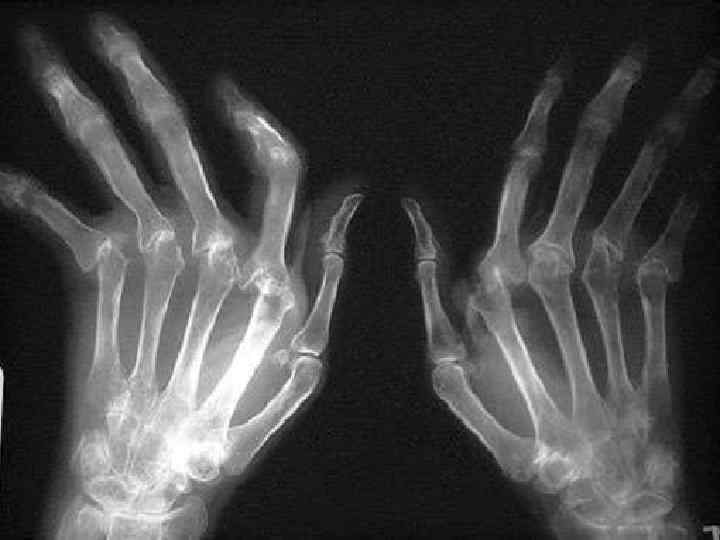

Инструментальная характеристика Рентгенологическая стадия (по Стейнброккеру, модификация) 1. Околосуставной остеопороз 2. Остеопороз + сужение суставной щели ± единичные эрозии 3. Признаки предыдущей стадии + множественные эрозии + подвывихи в суставах 4. Прихнаки предыдущей стадии + костный анкилоз

1. Больные, у которых имеются типичные для ревматоидного артрита эрозии на рентгенограммах. НО Однозначное определение ≪ типичной для ревматоидного артрита эрозии≫ до сих пор отсутствует.